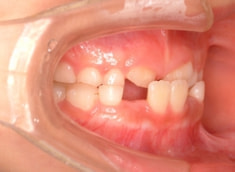

治療前

日本人の典型的なパターンである、上顎劣成長が顕著で、下顎骨体自体も大きい値を示しています。

Facial Axis(顔の成長方向):95.8°なので、今後下顎前突傾向は旺盛であると予測されます。

手根骨の骨年齢は実年齢よりも低く男児なので、今後旺盛な下顎の成長が予測されます。